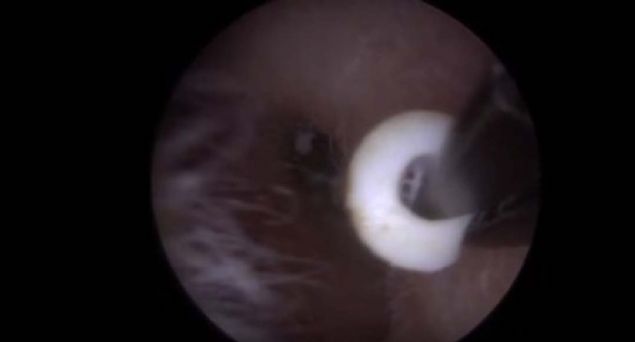

Kolundaki yaranın içinden çıkanlara kimse inanamadı!

Kolunda yara çıkan genç kadın sivilce zannedip önemsemedi ancak gerçek doktora gidince ortaya çıktı.

Yaranın içinden çıkan tropikal bölgede yaşayan ve larvalarını deri altına bırakan botfly cinsi sinekti.

Kolunda yara çıkan genç kadın sivilce zannedip önemsemedi ancak gerçek doktora gidince ortaya çıktı.

İşte o anlar...